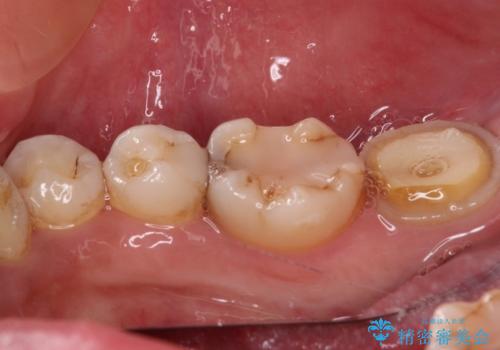

- かかりつけ医にて、歯の高さが不足しているためセラミッククラウンの装着はできないと言われたとのことで来院された患者様です。

診察したところ、確かに歯の高さは不足していましたが、土台の立て直しや歯の削り方を調整することでオールセラミッククラウンでも補綴可能と思われました。

ただし、クラウンの厚みは極力薄くした方が維持力が増すため、高強度のフルジルコニアクラウンにて補綴治療することとしました。

仮歯が途中外れることもなく、無事に補綴治療を行うことができました。

歯石や磨き残しなどが多いため、今後クリーニングを行っていきます。